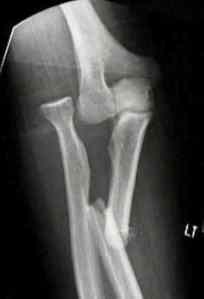

Fractures and Dislocations about the Elbow in the Paediatric Patient

Fracture-Dislocations of the Elbow in Adults